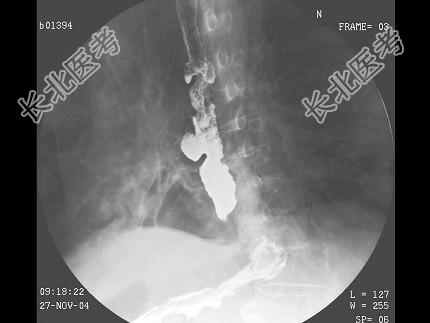

- 单项选择题男,71岁, 脾大、腹水、肝管结石2年,结合图像, 最可能的诊断为 ( )

E、食管癌